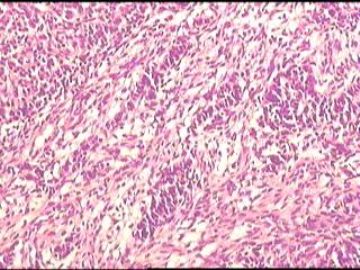

•25岁,女性,停经35周,发现腹腔包块1月余。

•手术所见:右侧卵巢肿瘤,12×8.6×8.0cm大小,表面光滑,内实质似鱼肉样、部分区域胶冻状,伴少许盆腔积水。

• 卵巢肿瘤图2

图2

性索间质来源的肿瘤。

先考虑卵泡膜

硬化性间质瘤